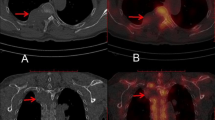

Now, we provide a brief discussion on the misclassified images by SPECS V21 provided in Fig. 11 as follows.

-

Random rotation significantly contributes to augmentation of the dataset while introducing errors in the receptive field (a small area of an image) between images for deep networks. Therefore, the rotation operation is mainly in charge of both the misclassified normal and metastasized images.

Difference in radiation dosage from person to person requests more personalized features to be extracted from a big dataset of SPECT bone images. For SPECT imaging, the absorption of radionuclide is inversely proportional to patient age, making metastasis images to be misclassified as normal. Therefore, some post-processing operations should be conducted after automatic classification, by taking the structural symmetry of human bones into consideration.